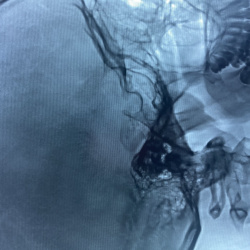

Здравствуйте, помогите с описанием, из анамнеза перенес операцию на левом ухе, жалобы болен длительно, из осмотра перфорация барабанной перепонки в мезотимпануме отделяемое гнойные с...